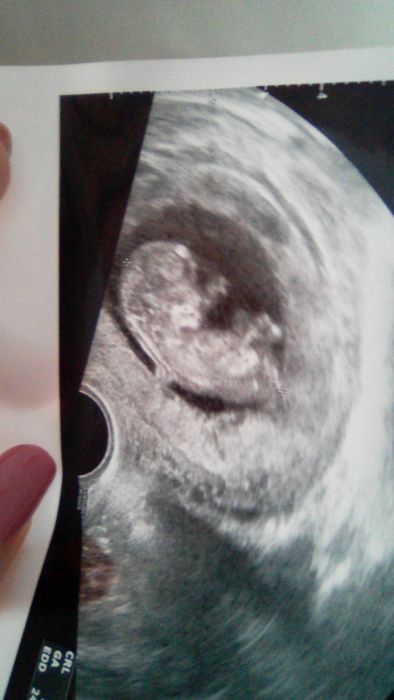

Jinak přikládám fotku ,jak miminko vypadalo ve 12 TT.